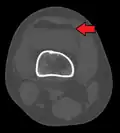

In all injuries to the tibial plateau radiographs (commonly called x-rays) are imperative. Computed tomography scans are not always necessary but are sometimes critical for evaluating degree of fracture and determining a treatment plan that would not be possible with plain radiographs.[10] Magnetic Resonance images are the diagnostic modality of choice when meniscal, ligamentous and soft tissue injuries are suspected.[11][12] CT angiography should be considered if there is alteration of the distal pulses or concern about arterial injury.

Lipohemarthrosis (presence of fat and blood from bone marrow in the joint space after an intraarticular fracture) seen on X-ray in a person with a subtle tibial plateau fracture -

Lipohemarthrosis due to a tibial plateau fracture -